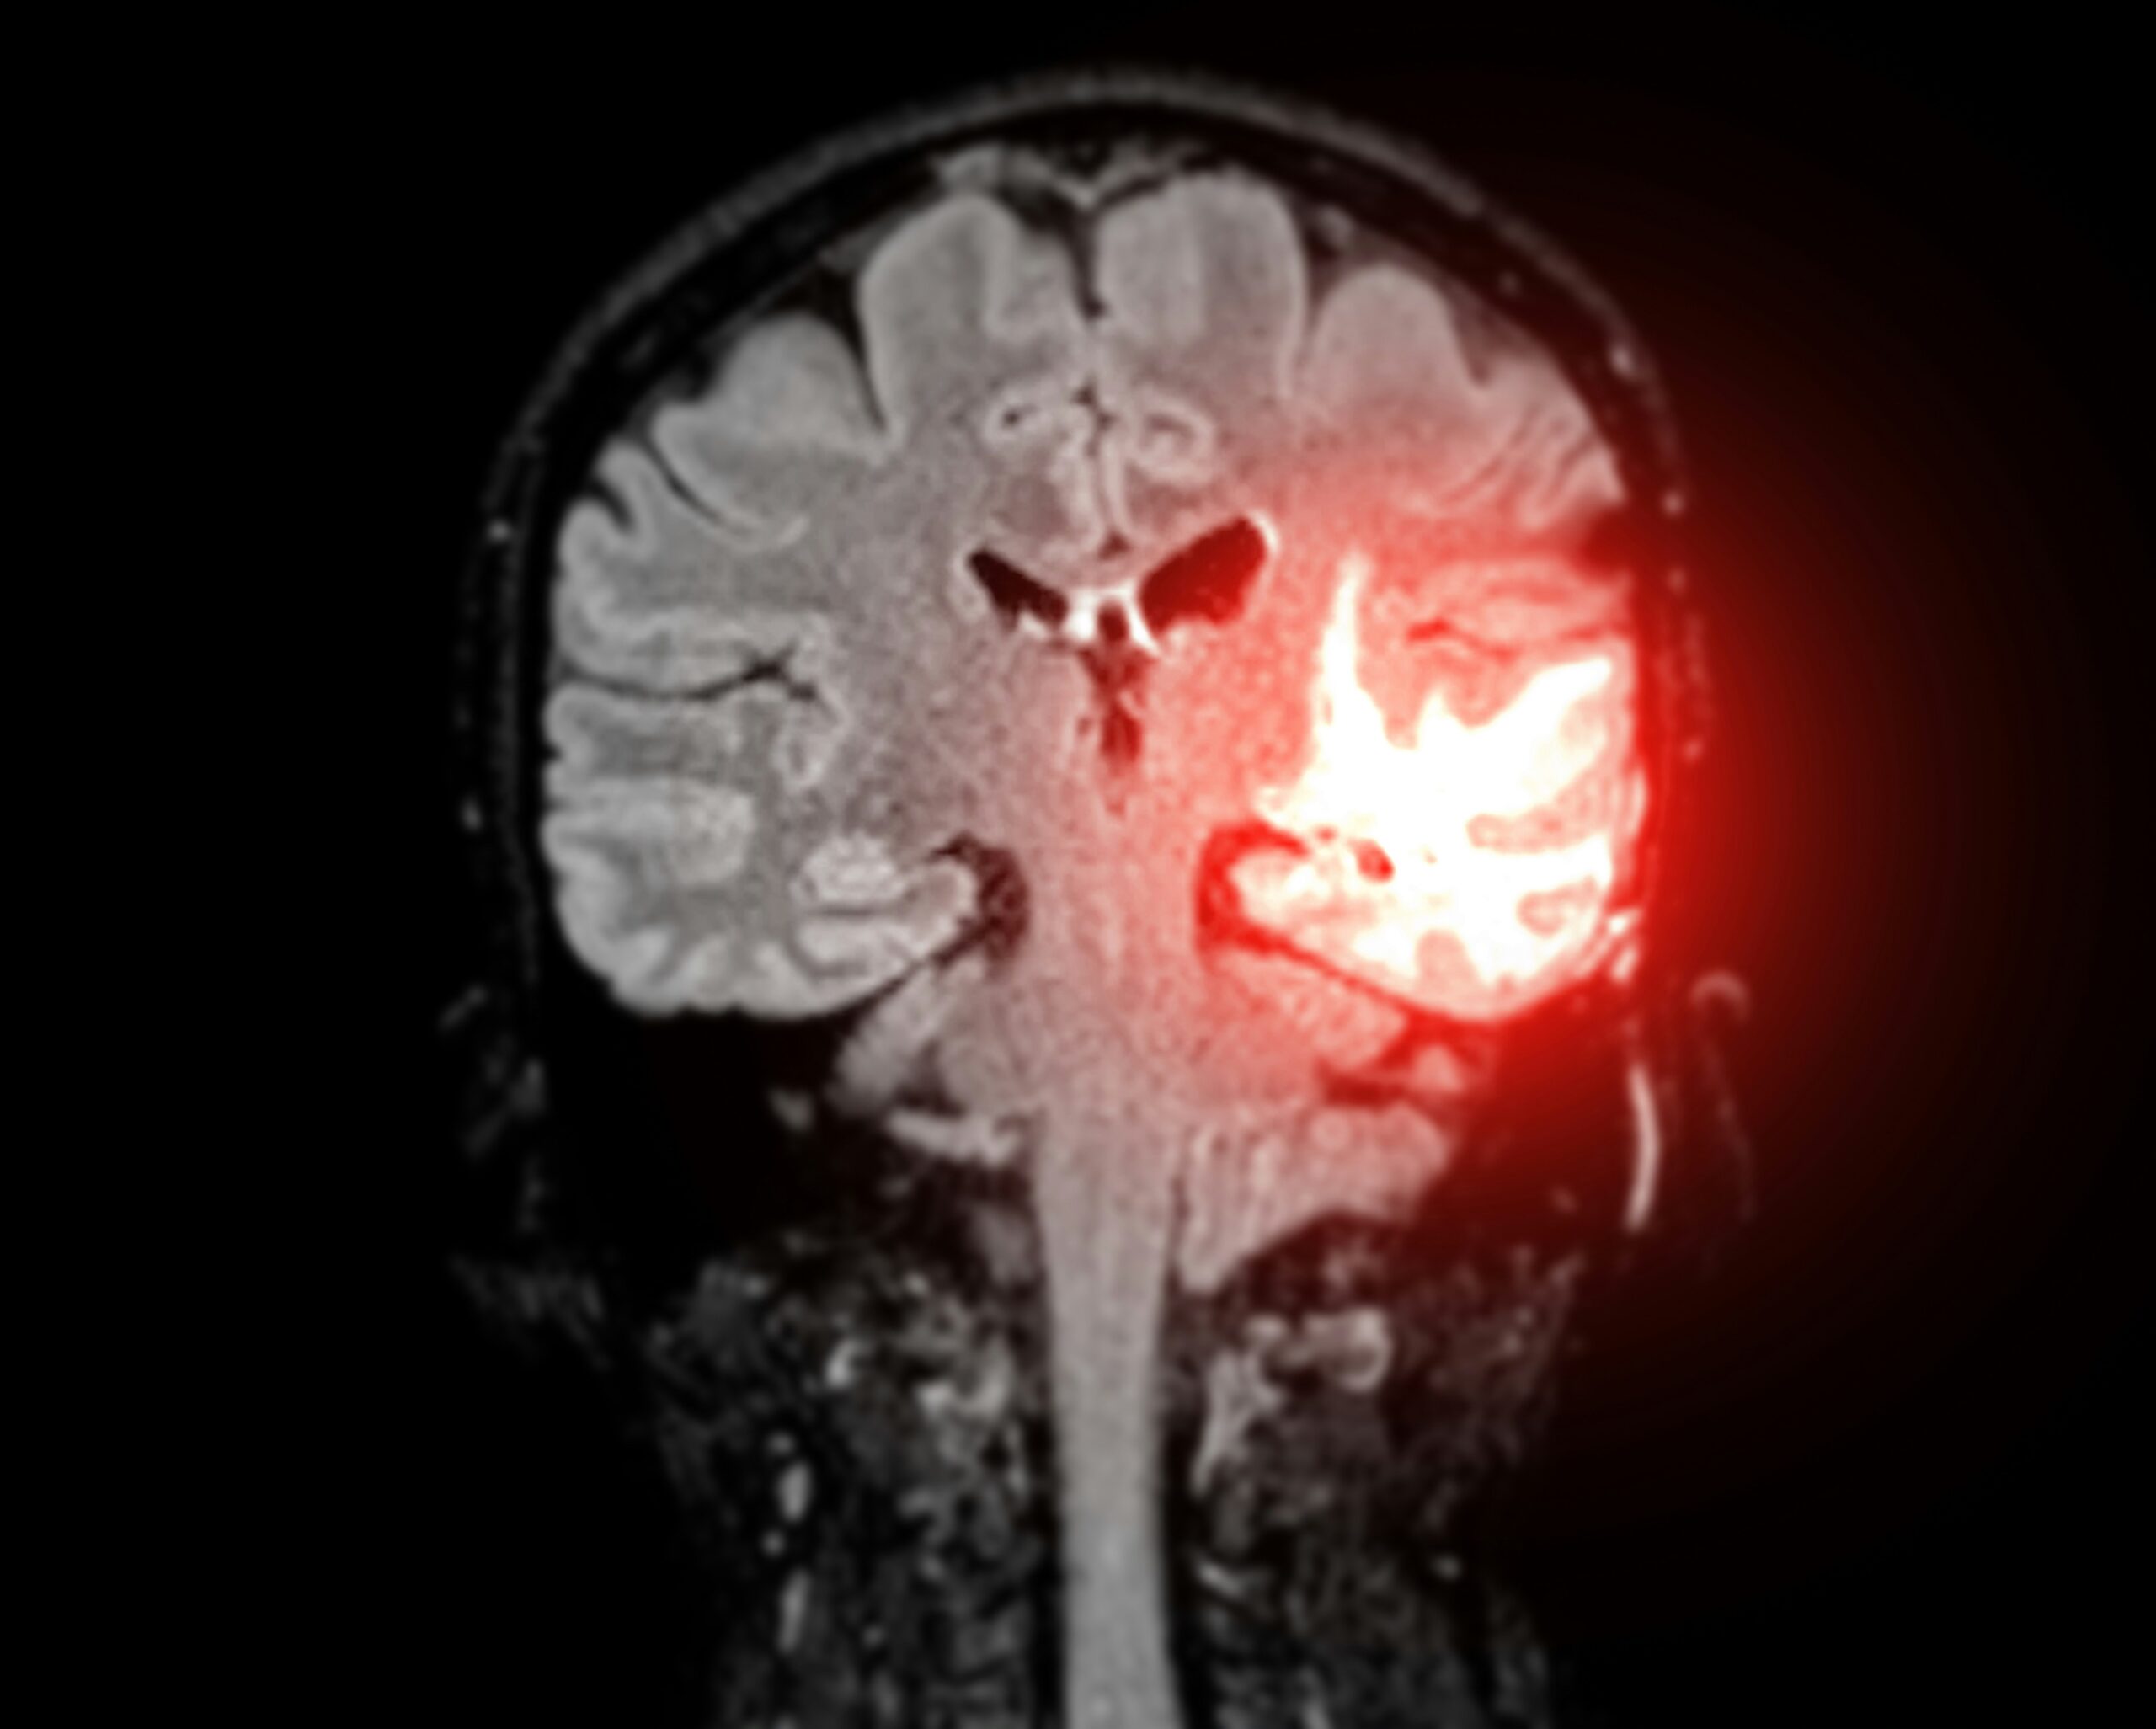

If you’ve been in a car accident and memory loss is one of the symptoms you’re experiencing, your doctor will likely run a few tests, beginning with standard blood tests and a physical exam. They may also schedule imaging tests like MRIs and CT scans to be able to spot brain abnormalities, such as lesions. You will likely undergo a neurological evaluation of your speech, vision, hearing, and reflexes.